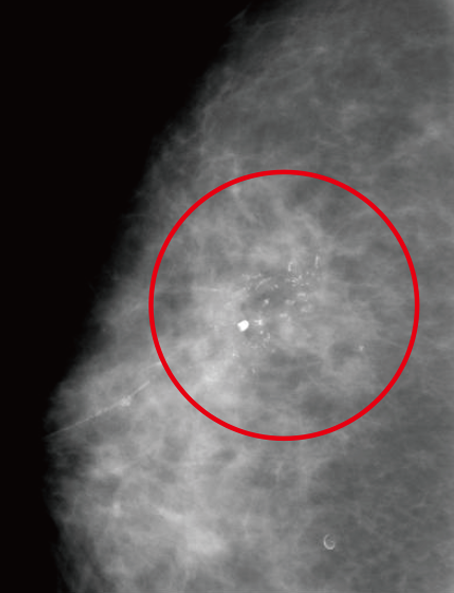

• 可藉由乳房篩檢攝影發現微小鈣化點等乳癌初期徵狀。

篩檢性乳房攝影 (Screening mammography)

左右兩側乳房各要照兩張X光片,分別為頭腳向(由上往下照)及斜位向(由側邊照)

• 結合電腦輔助偵測系統(Computer Aided Detection, CAD),加強了病灶判別功能。